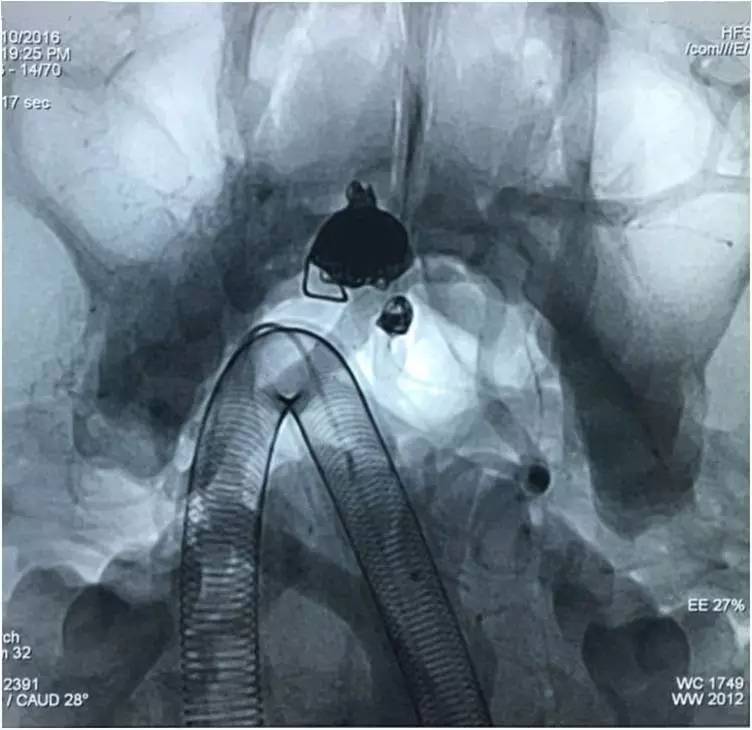

▼Headway17导入左PCA P2段,用于备放LVIS JR支架;Echelon10微导管送入基底动脉顶端动脉瘤瘤腔内,送入第一枚弹簧圈QC-4-12-3D,弹簧圈送出约一半长度,在瘤腔内盘旋,一定程度上能有助于防止后续释放的支架陷入瘤腔。

▼经预置的Headway17送入LVIS JR 3.5*23支架,跨瘤颈释放入左PCA-基底动脉内,蒙片显示支架张开良好。